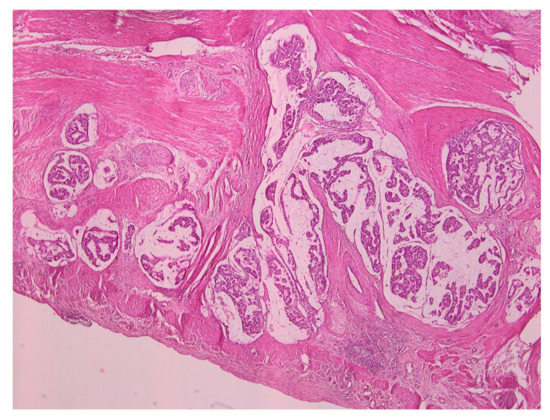

The histopathological examination revealed the presence of regional lymphangiomas, some with moderately differentiated adenocarcinoma metastasis and the rest with only a reactive aspect. The examination further revealed tumor deposits in peritumoral adipose tissue, intramural intravascular tumoral emboli, and histologically preserved epiploon, without malignant tumoral elements. Throughout the gastric mucosa, at different levels, numerous formations of sessile and semi-pediculate grayish polyploids with a histopathological appearance of tubular adenomatous polyp and tubules with light and moderate dysplasia were found. Figure 3 presents a representative image of the histopathological examination.

Figure 3. Histopathology examination of the gastric adenocarcinoma specimen.